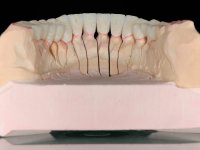

Foi proposto ao paciente fazer uma reabilitação total com infraestruturas em zircónia revestidas a cerâmica. No maxilar superior, seriam realizadas 6 coroas (1.3/1.2/1.1/2.1/2.2/2.3), uma ponte de 3 elementos (1.4/1.5/1.6) e uma ponte de 4 elementos (2.4/2.5/2.6 e 2.7). No maxilar inferior, foram propostas 7 coroas (4.3/4.2/4.1/3.1/3.2/3.5 /3.6) e duas pontes (4.4//4.5/4.6) e (3.3/3.4#/3.4).O objetivo seria subir a D.V.O., descruzar a mordida do lado direito, eliminar as infiltrações e as exposições radiculares e reabilitar o paciente com estruturas protéticas com aspeto mais natural.

Avaliada a situação inicial em conjunto com o médico dentista, foi considerado prioritário alterar a forma dos dentes, subir 1.5mm a D.V.O. e descruzar a mordida do 1º Quadrante. Na confeção da ponte provisória superior de acrílico com reforço metálico foram já ensaiadas essas alterações. Optamos por um monobloco de 13 dentes com o intuito de manter a estabilidade posicional dos dentes re- preparados. Após remoção das coroas e pontes antigas foi feita a re-preparação dentária. A ponte provisória foi rebasada em boca, primeiro com acrílico auto-polimerizável e depois com resina composta. Após 4 semanas de integração da ponte provisória superior foi confecionada a ponte provisória inferior, corrigindo-se finalmente as discrepâncias existentes no plano oclusal. As impressões foram realizadas com a técnica de dupla mistura, com dupla mistura. Simultaneamente foram feitos os registos da relação inter-maxilar e da relação do maxilar superior com a base do crânio, utilizando o arco facial. Montados os modelos de trabalho em articulador semi-ajustável, foram confecionadas as peças próteticas, utilizando tecnologia CAD-CAM para a realização das infra-estruturas em zircónia. A colocação da cerâmica foi feita procurando que a forma dos dentes reproduzisse uma forma anatómica natural. A tonalidade foi condicionada pela vontade do paciente. Foi feita uma prova com a cerâmica em “biscuit” para verificação técnica e validação estética. Após aprovação pelo paciente o trabalho foi finalizado e colocado em boca.